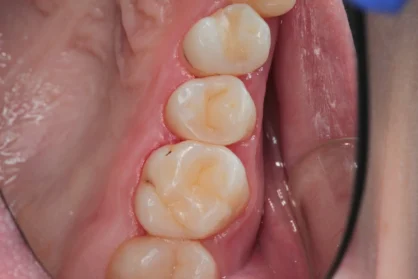

Приклади робіт лікаря-стоматолога

Естетична реставрація. До / після